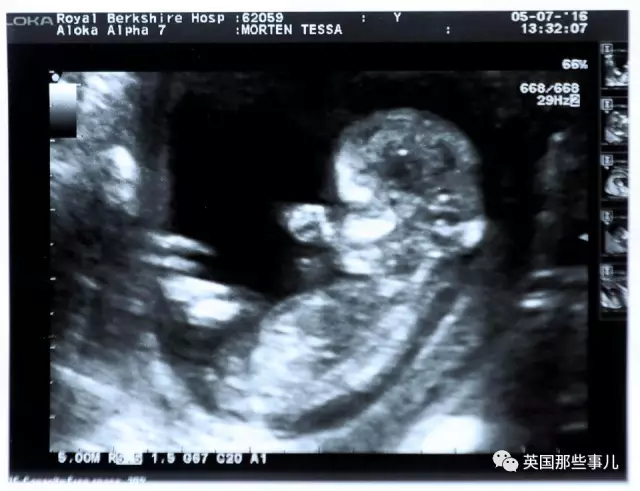

然而,在Tess夫妇忐忑不安地等待诊断结果时, 奇迹就这样发生了… 在一次B超检查中,Tess原本十分忐忑的躺在病床上, 可医生突然把显示器转到了Tess的视线方向,十分激动的指着图像说: “你的卵巢没有问题,但我想你需要看看这个。” Tess十分不解的望向屏幕, 就这样,她在B超图中看到了一个婴儿,她几乎脱口而出: “啊,这是我的吗?”

这?已经绝经近7年还能怀孕??!! 那一刻的Tess彻底震惊了, 原本,她紧紧握着一旁护士的手,担心着最坏的消息, 可她万万没想到,自己竟然是怀孕了??!!

“我哭了,我从来没想过这事儿会发生,我已经绝经了,我明明不可能怀孕的。” 现在回忆起来,Tess依然难掩激动…

回到家后,Tess立马把这个喜讯告诉了Neil: “那天Neil要上班所以没和我一起去医院,他很担心,因为我一直没有回电话, 当我看到他的时候,我低声说,不是癌症,是我肚子里有小宝宝了。“ 显然,Neil也觉得非常不可思议,俩人一边开心不已, 另一边,又非常担心搞出什么乌龙, 第二天,他们又去重新检查了一次: “结果仍然是好的,那时我已经怀孕三个月了,是个可爱的小女孩, 后来,因为我们年纪都比较大了,我们又做了很多测试,好在,一切都正常健康…”